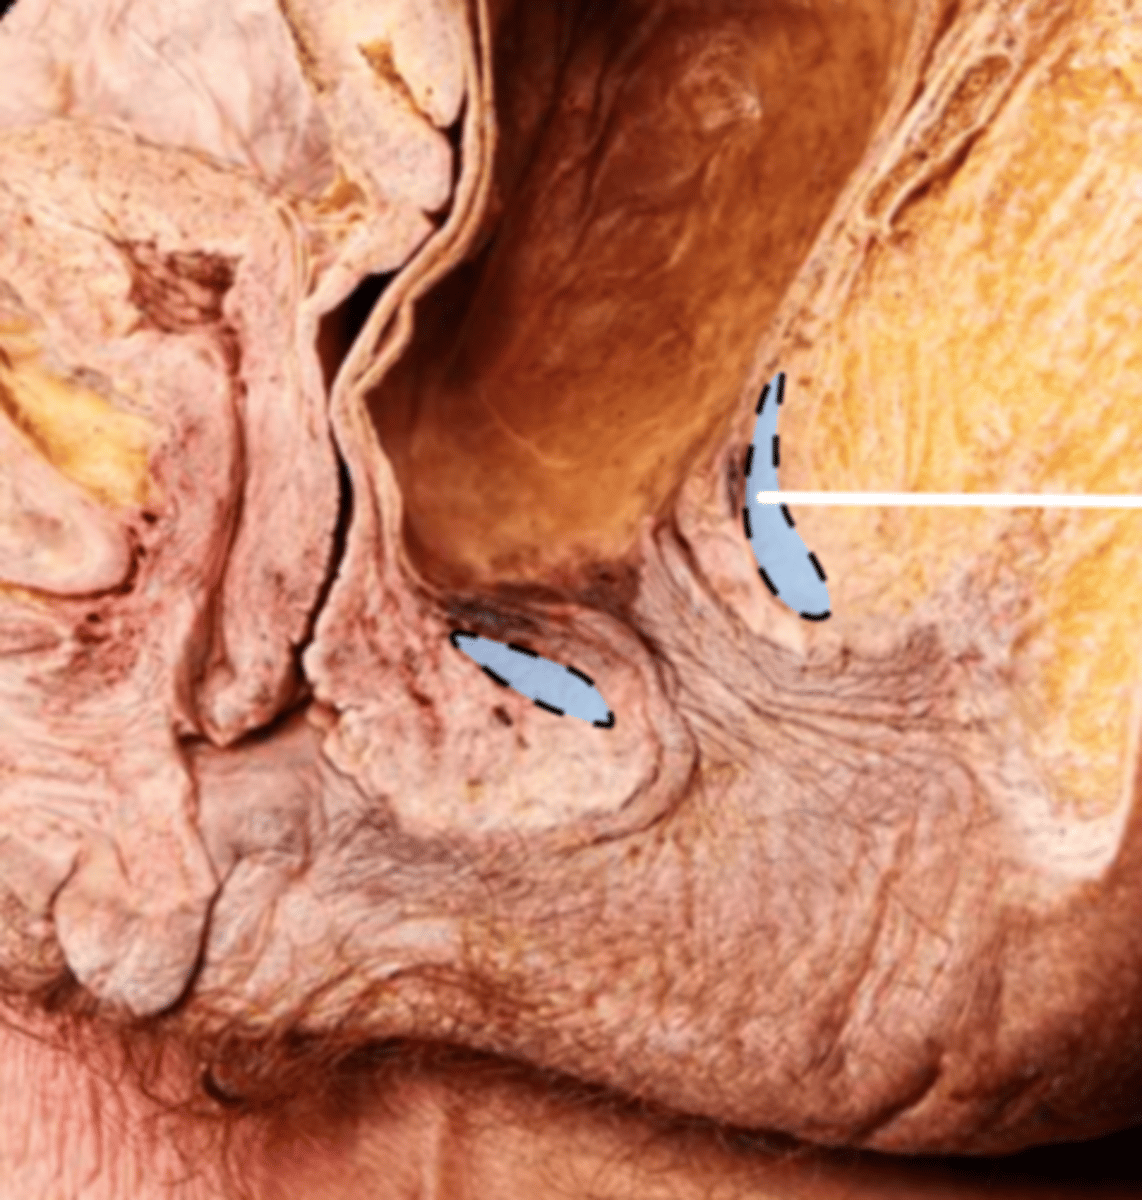

Rectum

Anal Canal

Internal Anal Sphincter

External Anal Sphincter